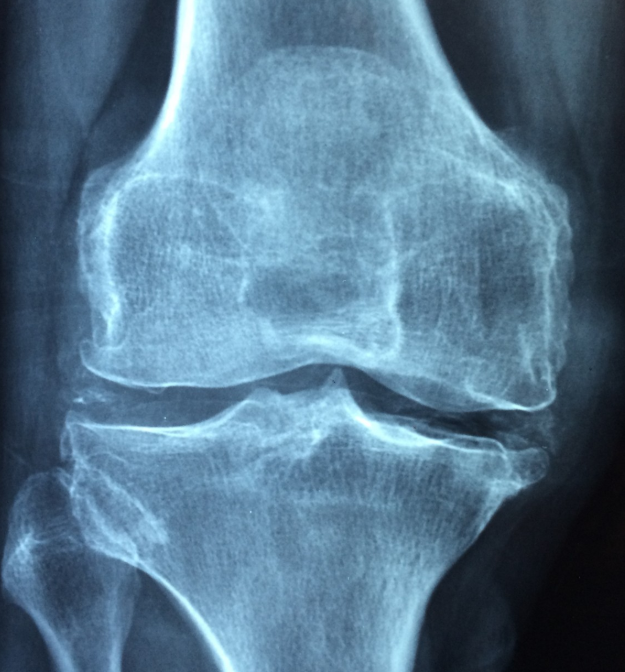

- 뼈 건강 유지 – 골밀도 강화 및 골다공증 예방

- 골밀도 감소 및 골다공증 위험 증가